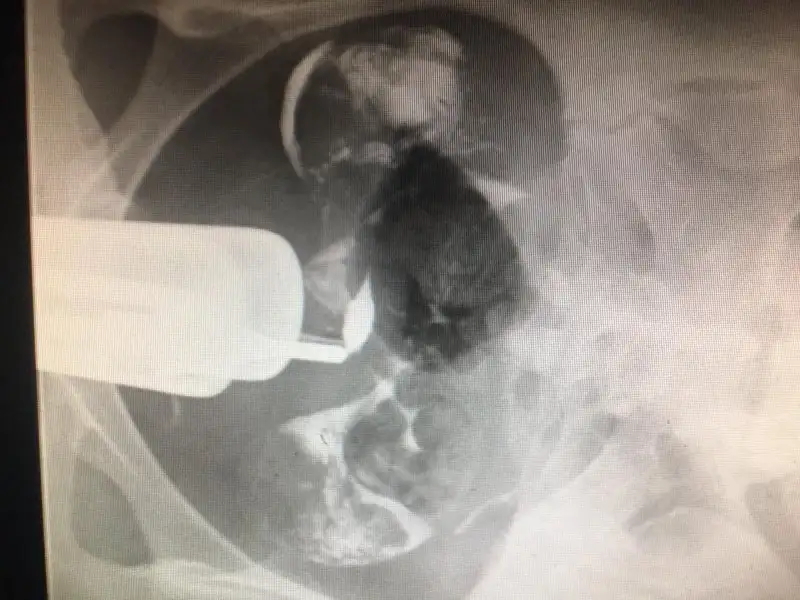

bu benim rahim filimimNapdin canım ? Nasıl gecdi ?